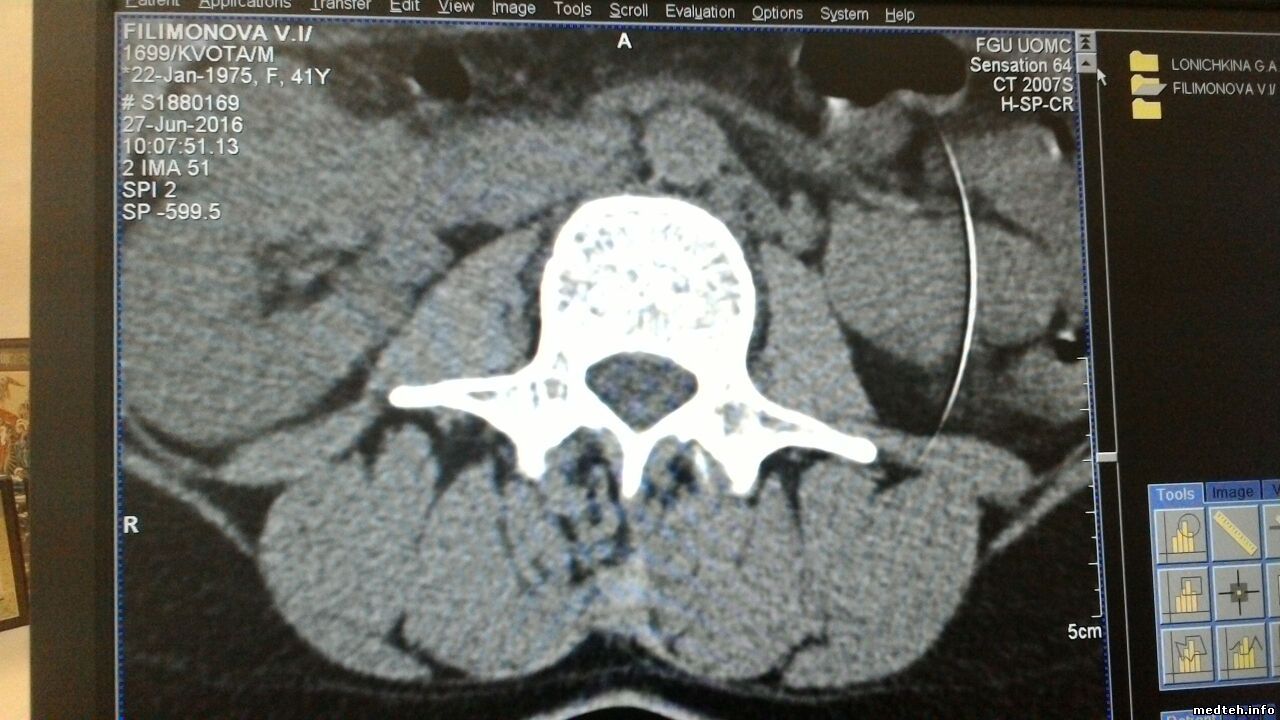

dunakanДата: Понедельник, 27.Июн.2016, 21:07 | Сообщение # 17

Коллеги, мож кто чего подскажет

сен 64, много битых модулей, порядка 10 маст екчендж, заменили, при выполнение дифектив ченнел , проходит проwедуру но не все может записать в таблицу.

делаем тюн ап , (для модулей, наиболее полный), все проходит до дефектив ченелз, после этого пункта то же все проходит.

из з ане полной записи таблиц артефакт слабый на изображение.

вручную таблицы удалял, бэк апов нет, почему то , старые дифектив ченалз накатывал, з позитион проходит, причем до замены детекторов дефектив делал нормально....

кто что может подсказать?

7503504.jpg (232.0 Kb) · 2332555.jpg (135.0 Kb)